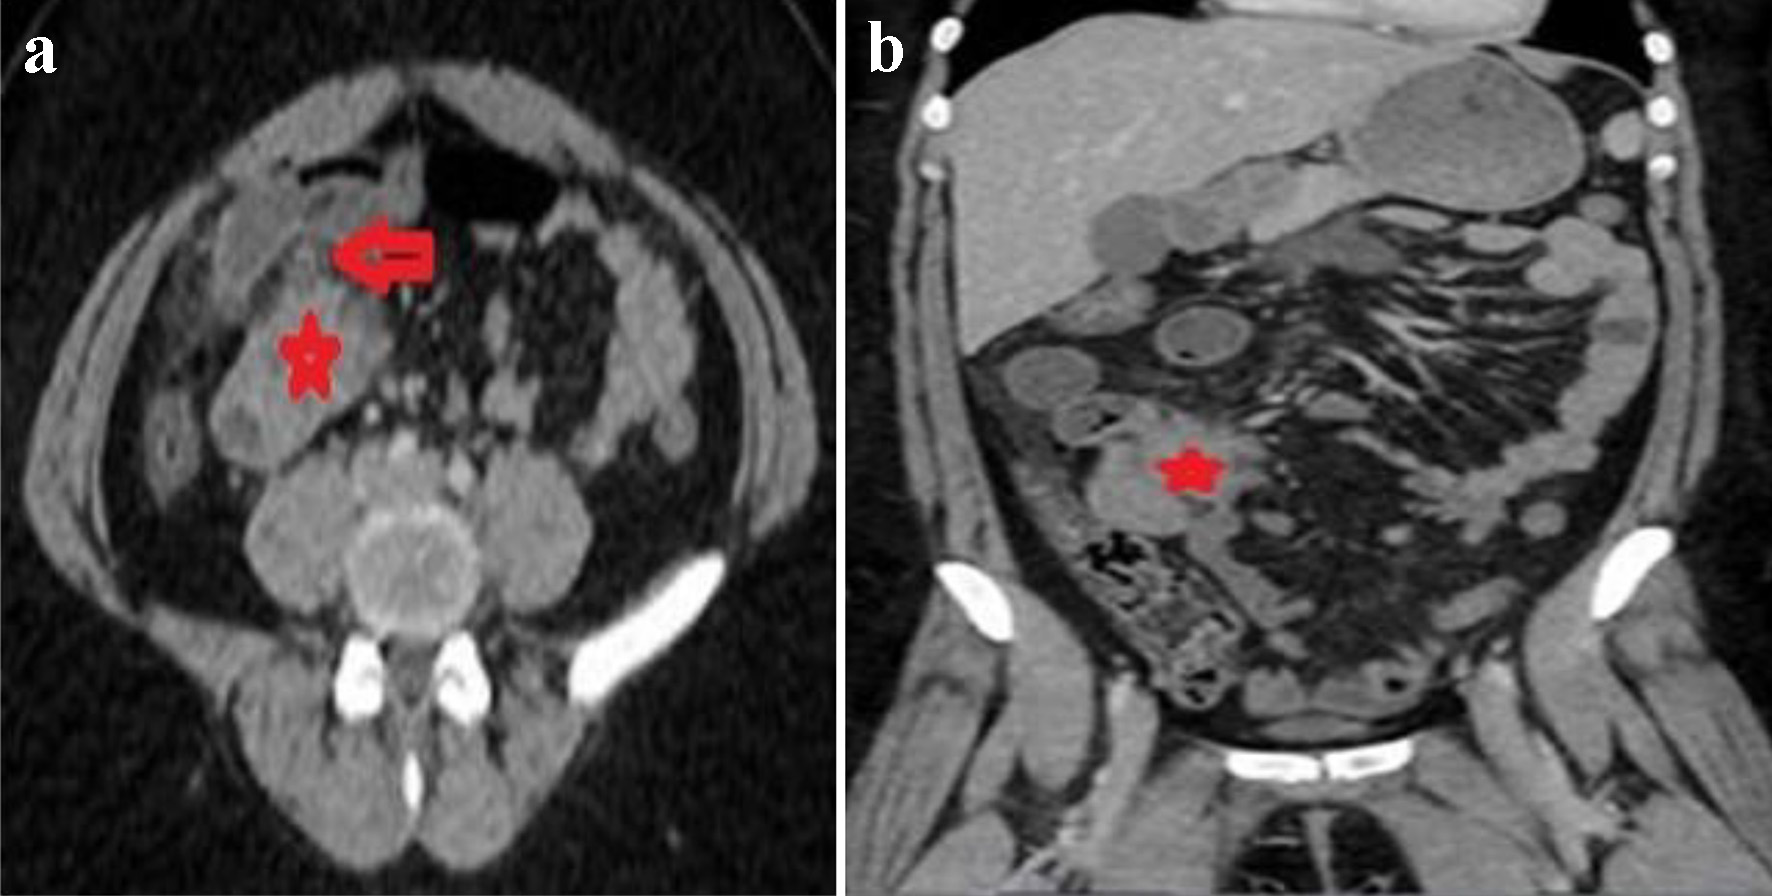

A computer tomography (CT) of the abdomen demonstrated a small bowel obstruction with dilated small loops of bowel with a transition point on the right of the mid-abdominal region at a spiculated mass arising in the distal ileum, measuring about 4.0 × 3.9 × 4.4 cm, along with mild fat stranding and local inflammatory changes, simulating small bowel carcinoid tumors (Fig. 1a, b). Patient was admitted for small bowel obstruction along with intractable pain and was urgently taken for an exploratory laparoscopy. A 3 × 3 cm mass was visualized in the distal ileum adhering to the associated mesentery, with an edematous and puckered look. The mass was resected with primary bowel anastomosis, and the postoperative course was uneventful.

![]() Click for large image | Figure 1. Axial (a) and coronal (b) images of CT of abdomen revealing mildly dilated small bowel loops with a transition point to the right of the midline (red arrow in a) in an area of a spiculated mass in the distal ileum simulating carcinoid tumors (red stars in a and b). CT: computed tomography. |